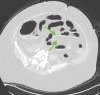

The prothrombotic nature of severe acute respiratory syndrome coronavirus 2 (SARS-CoV-2) has been well-established since the start of the global coronavirus disease 2019 (COVID-19) pandemic. Mesenteric artery thrombosis and acute mesenteric ischemia are, on their own, rare occurrences and often present with fatal gastrointestinal (GI) pathologies requiring quick identification and intervention by the clinician to improve clinical outcomes. SARS-CoV-2 infection can present with acute GI pathologies and warrants further investigation regarding anticoagulation therapy in COVID-19 positive patients. We report on a 64-year-old woman infected with SARS-CoV-2 who presented with superior mesenteric artery thrombosis and acute intestinal ischemia.